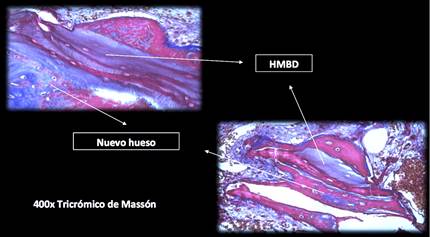

El estudio histológico e histomorfométrico se realizó en el laboratorio de Anatomía Patológica de la Facultad de Odontología de la UdelaR. Las muestras se colocaron en una solución de formol buffer tamponado al 10% con un pH 6,5 para su preservación y para el procesamiento técnico de inclusión en parafina, previa descalcificación de los mismos. Las piezas fueron sometidas a una solución de Ion-Exchange DecalUnit (I.E.D.) de Biocare Medical, por 24 horas para su descalcificación. El sistema de descalcificación I.E.D. incorpora una resina catiónica de intercambio iónico fuerte en una solución de ácido débil, para eliminar los iones de calcio del tejido óseo para su sustitución por iones hidrógeno. El proceso de intercambio iónico no requiere soluciones concentradas de ácidos fuertes como en los métodos de descalcificación tradicionales, las estructuras celulares delicadas permanecen intactas, lo que mejora su observación microscópica. Los cilindros óseos descalcificados se seccionaron longitudinalmente por su eje central con una cuchilla de micrótomo, obteniéndose de cada espécimen dos fragmentos óseos con una superficie de corte del sector central del cilindro. (Fig. 4)

El procesamiento se realizó en un procesador automático de tejidos marca SLEE Thermo, utilizando 7 estaciones, cinco de ellas en alcoholes de graduación creciente hasta llegar al alcohol isopropílico al 100% y dos de parafina.Obtenidos los bloques de parafina se realizaron los cortes histológicos seriados de 4um y luego se colorearon con Hematoxilina Eosina. Las láminas fueron codificadas con números ordinales continuos a partir del 1 para mantener la confidencialidad de los pacientes y para cegar a los observadores para el análisis histológico. De esta forma desconocían el tipo de injerto óseo (partículas de Bio-Oss® S o L) colocado en cada paciente. El análisis histológico se realizó en un microscopio óptico binocular Olympus BX 50, por un solo observador, ciego calibrado y experiente en la observación de las piezas. Las imágenes microscópicas de las laminillas fueron capturadas con una cámara de video Infynit1, acoplada al microscopio binocular, se utilizó el software Image Pro Plus ® versión 7.0. para capturar las imágenes y la herramienta Live Tiling del software para escanear la laminilla, obteniendo una imagen total del cilindro óseo con una magnificación de 10x. (Fig. 5)

Para el análisis histomorfométrico, se evaluaron las imágenes distinguiendo el tejido óseo vital de neoformación, el tejido blando no mineralizado (médula ósea, tejido conjuntivo, etc.) y el material de injerto. La diferenciación de hueso vital de neoformación, con respecto al material de injerto y otras estructuras, se realizó evaluando las características de hueso con las tinciones utilizadas y la presencia de osteocitos.El material de injerto se identificó por la ausencia de osteocitos. Se midió el área total del cilindro óseo y subsecuentemente las diferentes áreas mencionadas anteriormente, obteniéndose un valor expresado en porcentajes.Para este análisis, se realizó la identificación de las áreas por dos observadores ciegos calibrados. Para cuantificar el porcentaje de las diferentes áreas se trabajó con el software de edición de imagen Raster Adobe Photoshop CS5.Del área total del cilindro óseo se substrajeron los espacios en blanco, que correspondían a zonas de contracción del tejido consecutivas al procesamiento histológico. Los demás tejidos fueron identificados con un color diferente y medidos sus porcentajes por el software de edición de imágenes. Los porcentajes de cada tejido y del material de injerto se expresan en la siguiente tabla. (Fig. 6)